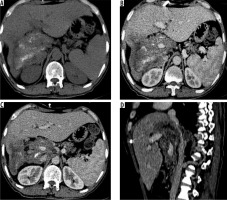

Figure 5

A) Axial non-contrast computed tomography (CT) image through upper abdomen reveals a large heterogeneous mass involving whole right lobe with scattered matrix calcifications with capsular retraction. Portal phase contrast-enhanced axial CT images (B, C) at slightly different levels reveal no enhancement of mass. B, C) Mass shows infiltration of hepatic hilum with encasement of portal vein, common bile duct, and hepatic artery. D) Sagittal post-contrast CT image clearly shows encasement of intra hepatic IVC (P4 disease)

Figure 6

Axial non-contrast computed tomography (CT) (A) and post-contrast CT (B) images reveal infiltration of diaphragm and right adrenal gland (arrows) (N1 disease). C) Axial contrast enhanced image in another patient shows infiltration of parietal wall (arrow) (N1 disease). D) Axial contrast-enhanced CT image in a young boy shows metastatic involvement of left lung (M1 disease)